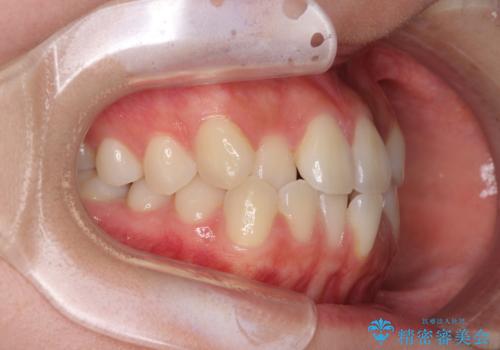

- 前歯のクロスバイトが気になり、インビザラインによる矯正治療を希望して来院された患者様です。

上顎側切歯(上の真ん中から2番目の歯)が舌側転位している場合、インビザラインでは仕上げきれないことが多く、更には無理して動かそうとすると歯髄壊死を起こすリスクが高いと言われています。

インビザラインで歯列を移動する前に、上顎前歯をワイヤー矯正で整え、その後上下歯列をインビザラインにて矯正治療を行うこととしました。

舌側転位している側切歯特有の、切縁の位置が不揃いであったり、根元が内側に引っ込んだ状態であったりという、インビザライン独特の仕上がりになることなく、きれいに整った歯列とすることができました。